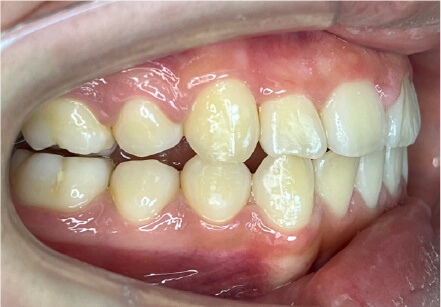

叢生の症例

41歳

/

女性

相談内容

横から見た時のガタガタが気になる

カウンセリング・診断結果

インビザライン、正中は上11に合わせていく、抜歯・拡大装置・IPR・アタッチメントOK

治療内容・方法

アライナー矯正

術後の経過・現在の様子

クリアライナー使用

治療のリスク

痛み・歯根吸収・歯肉退縮・虫歯・後戻り

費用・治療期間

880,000円、7ヶ月

トレーニングなど